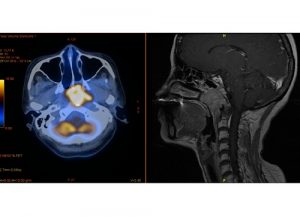

Covid-Impfung verbessert Wirkung von Krebstherapie10. November 2022 Nasenrachentumore (gelb markiert) sind in Ländern Südostasiens eine häufige Erkrankung. Die Sorge, die Therapie könne ungünstig mit einer Covid-Impfung interferieren, ist aber wohl unbegründet. Abbildung: ©Y.J. Hua / Sun Yat-sen University Cancer Center Menschen mit Nasenrachenkrebs werden häufig mit Immuncheckpoint-Inhibitoren behandelt. Bislang befürchtete man, dass eine Impfung gegen COVID-19 den Erfolg der Krebstherapie mindern oder starke Nebenwirkungen hervorrufen könnte. Eine aktuelle Studie der Universitäten Bonn und Shanxi in der Volksrepublik China gibt diesbezüglich nun Entwarnung. Viele Krebszellen sind dazu in der Lage, die Immunantwort des Körpers zu unterlaufen. Sie betätigen dazu eine Art Knopf auf den Immunzellen, den PD-1-Rezeptor. Dadurch schalten sie diese körpereigenen Abwehrtruppen gewissermaßen ab. Mit Medikamenten lassen sich die PD-1-Rezeptoren blockieren. Das Immunsystem kann so den Tumor besser bekämpfen.Bei der Impfung gegen Covid wird ebenfalls die Immunantwort stimuliert, wobei der PD-1-Rezeptor involviert ist. „Man befürchtete, dass die Impfung sich nicht mit einer Anti-PD-1-Therapie vertragen könnte“, erklärt Dr. Jian Li vom Institut für Molekulare Medizin und Experimentelle Immunologie (IMMEI) am Universitätsklinikum Bonn. „Diese Gefahr besteht insbesondere bei Nasenrachenkrebs, der genau wie das SARS-Cov-2-Virus die oberen Atemwege befällt.“Der Bioinformatiker hat nun zusammen mit Kooperationspartnern aus der Volksrepublik China untersucht, ob diese Sorge berechtigt ist. An der Analyse nahmen mehr als 1500 Patienten teil, die in 23 Krankenhäusern aus ganz China behandelt wurden. Derartige Multi-Center-Studien gelten als besonders aussagekräftig, da die Teilnehmenden sehr unterschiedlich sind und die Ergebnisse zudem nicht durch regionale Eigenheiten verfälscht werden.Geimpfte sprachen besser auf Krebstherapie anEine Teilgruppe von 373 Betroffenen war mit dem chinesischen Covid-Vakzin SinoVac geimpft worden. „Erstaunlicherweise sprachen sie deutlich besser auf die Anti-PD-1-Therapie an als die Ungeimpften“, erklärt Prof. Christan Kurts, Direktor des IMMEI und Mitglied im Transdisziplinären Forschungsbereich „Life & Health“ sowie im Exzellenzcluster ImmunoSensation. „Es kam bei ihnen zudem nicht öfter zu schweren Nebenwirkungen.“ Warum die Behandlung nach der Vakzinierung erfolgreicher war, können die Forschenden nicht sagen. „Wir nehmen an, dass durch die Impfung bestimmte Immunzellen aktiviert werden, die dann den Tumor attackieren“, sagt Prof. Qi Mei vom Universitätsklinikum Shanxi. „Wir werden dieser Hypothese nun weiter nachgehen.“Nasenrachenkrebs ist hierzulande recht selten. In Südchina und anderen Ländern Südostasiens ist die Erkrankung dagegen weit verbreitet. Als Gründe vermutet man unter anderem den häufigen Einsatz von Klimaanlagen in den feuchten und heißen Regionen. Auch Ernährungsfaktoren scheinen eine wichtige Rolle zu spielen. In Taiwan gilt Nasenrachenkrebs inzwischen bei jungen Männern als eine der häufigsten Todesursachen.Beteiligte Institutionen und Förderung:An der Arbeit waren neben der Universität und dem Universitätsklinikum Bonn die Shanxi Medical University sowie das Tongji Medical College beteiligt. Zudem kooperierten die Forschenden mit einer Reihe von Kliniken in ganz China. Die Studie wurde durch das Chinesisch-Deutsche Zentrum für Forschungsförderung (SGC), das Exzellenzcluster ImmunoSensation² der DFG sowie das Bundesministerium für Bildung und Forschung (BMBF) gefördert.